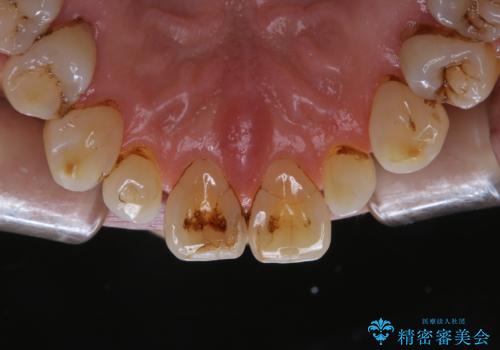

- クリーニングがかなり久しぶりで、全体的にきれいにして欲しいとのことで来院されました。全体的にステインの量がとても多かったため、施術前にご相談をし、60分コースでできる限りのステイン落としを行うこととなりました。今回は審美的に見える表側をメインでPMTCを行いました。

毎日丁寧に歯磨きをしていても、日常生活での飲食物などにより着色してしまうことはあります。PMTCでは、歯の表面の凸凹にミネラルを補給して、ツルツルの表面に仕上げます。定期的にPMTCを行うことにより、歯質の強化になり着色がつきにくい状態になります。